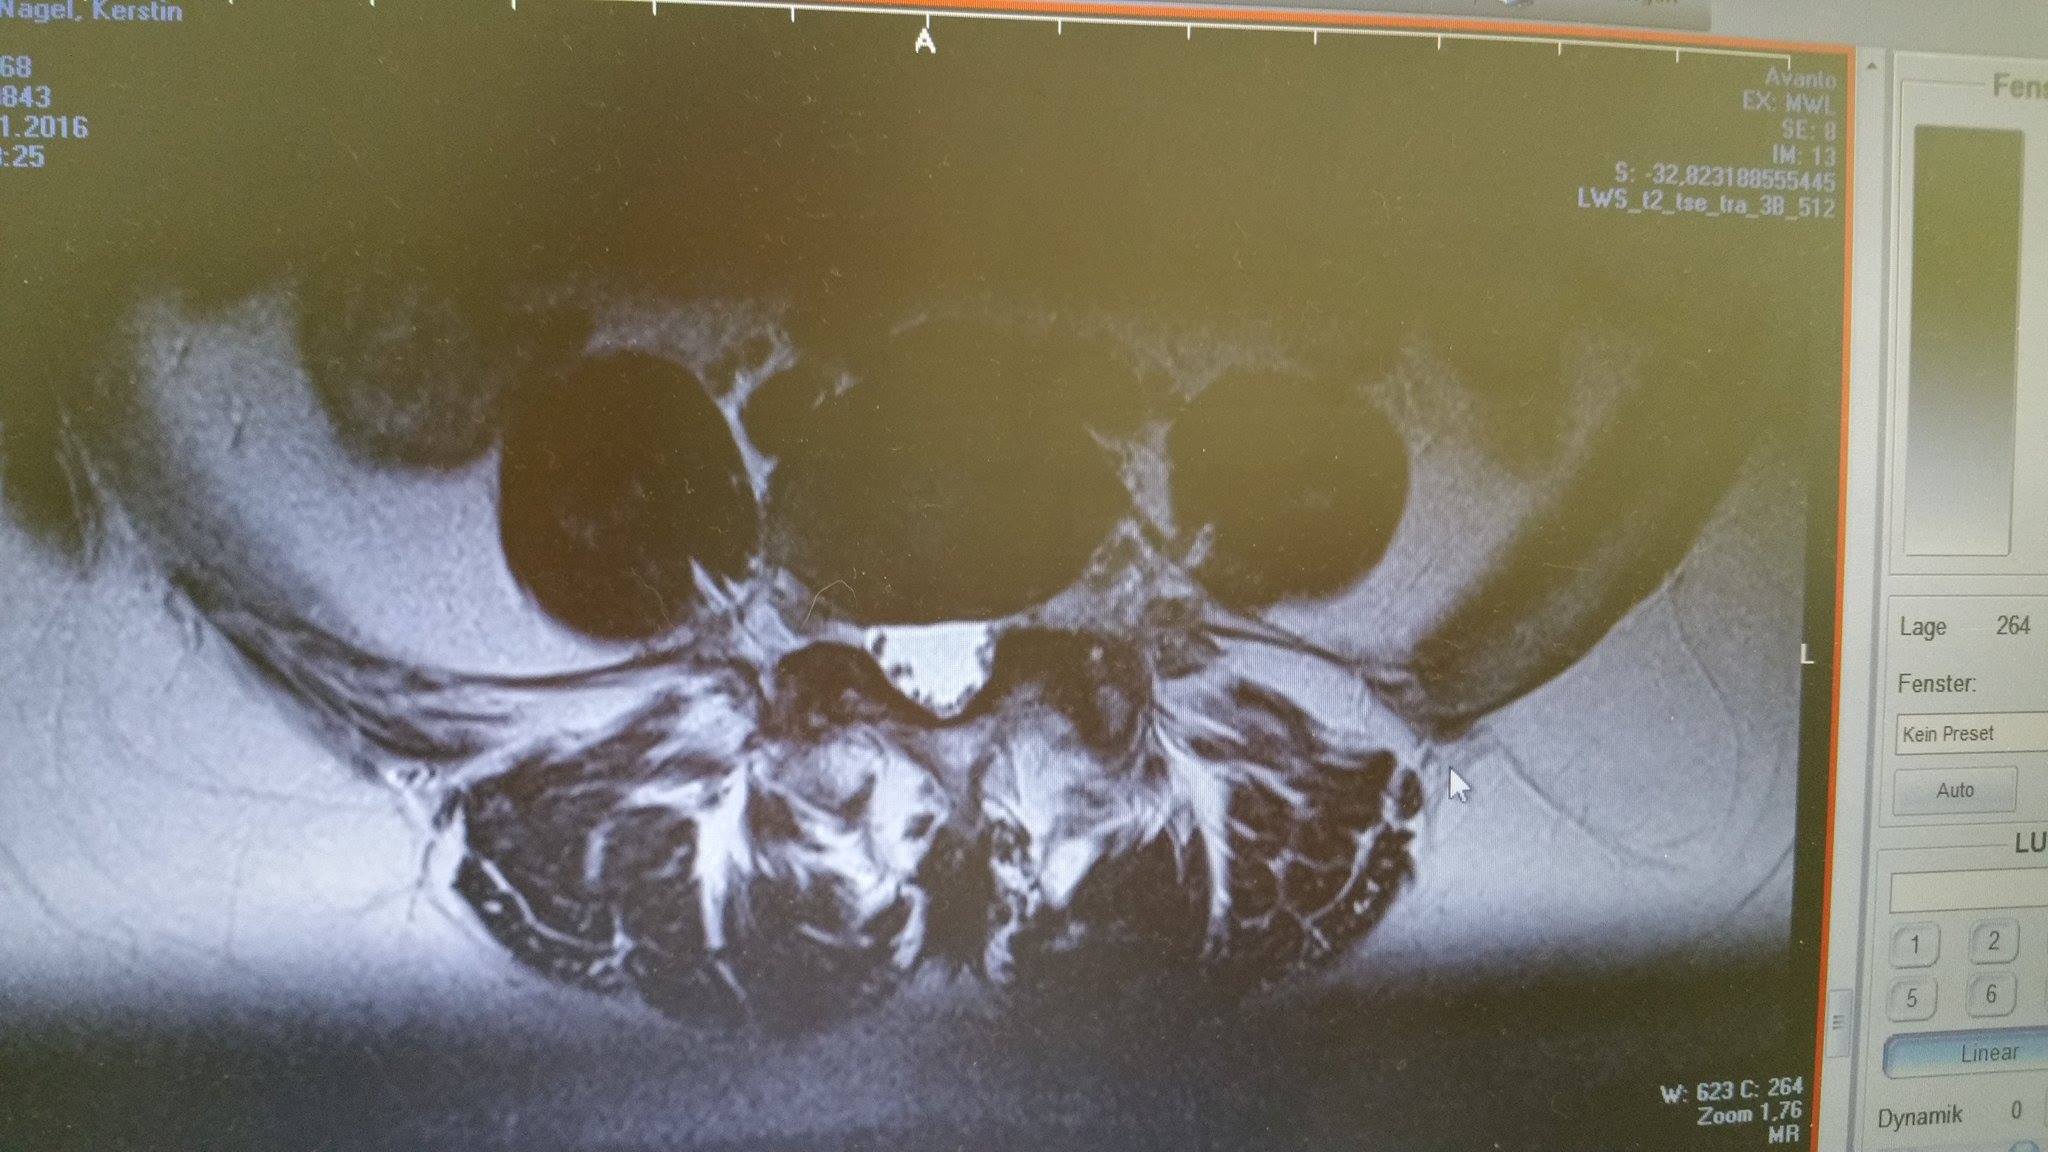

Daraus können schließlich die MRT Bilder (Schnittbilder) erzeugt werden. Dadurch entstehen verschieden aussehende Bilder. ▶ MRT in Oberhausen Kontaktdaten ⏲ Öffnungszeiten Bewertungen Das Telefonbuch Ihre. Leider ist alles unverändert bzw. schlimmer geworden.

MRT-Bilder schenken uns Einblicke ins menschliche Gehirn. Schonende Methode: Die MRT-Untersuchung im "Kernspin" kommt ohne. Eine MRT (Kopf- und Halsbereich) wird vor allem in der Neurologie durchgeführt, um krankhafte Veränderungen oder Verletzungen im Schädelbereich festzustellen.